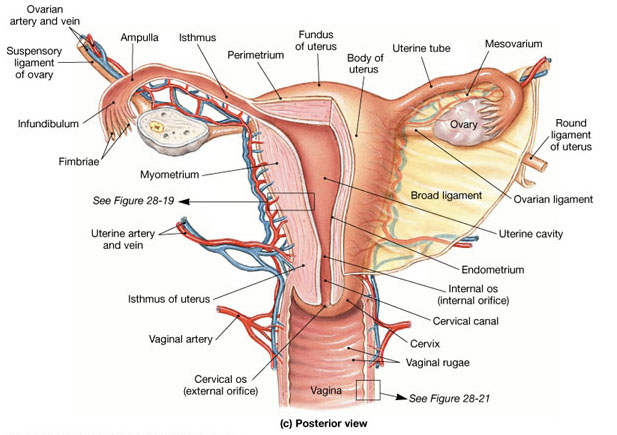

Cervix

Anatomy and Histology

Divided into portio vaginalis and portio supravaginalis

Ectocervix - lined by stratified squamous cells

- found on the outer portion of cervix up to the squamocolumnar junction of the external os

- divided in basal, parabasal, intermediate and superficial layers

-- basal layer: dense chromatin in picket-fence pattern which are mitotically inactive and are Ki-67 neg

-- parabasal cells are a little bigger than basal layer cells bc have more cytoplasm; their nuclei are less condensed, they are mitotically active, thus (+) Ki67

-- intermediate cells have lots of clear cytoplasm from glycogen accumulation (don't confuse c koilocytes!!), have more vesicular nuclei

- superficial cells also have lots of clear cytoplasm, but have smaller rounder nuclei

-- superficial cells predominate c lots of estrogen, while intermediate cells seen more after ovulation

- can see hair follicles or other glands in ectocerivix

External os is slit-shaped in parous women

Squamocolumnar junction - found at the external os in prepubertal women, moves a little outward at menarche, and then moves up, as squamocolumnar metaplasia, toward internal os during reproductive years, then goes back out again towards external os again nearing menopause

- may undergo squamous epithelialization where squames go under glands and push them up and out; or can undergo squamous metaplasia where endothelial reserve cells proliferate

-- immature squamous metaplasia may look dysplastic, bc the cells have inc NC, lack maturation, and are hyperchromatic, but they are also relatively uniform c smooth nuclear contours (a Ki67 may help to differentiate [<15% in basal / surface cells of squamous metaplasia])

- transitional metaplasia resembles urothelium and has hyperplastic epithelium w/o maturation, inc NC, uniform oval nuclei c lots of grooves, no nucleoli, and swirling architecture, is usually assic c atrophy and will be (+) CK13/17/18 but CK20 neg

Endocervix - simple columnar mucinous cells c small compact basal nuclei (which can move apical during menses); ciliation increases towards internal os

- begins at the external os and ends at the internal os

- bcl-2 and CK17 decreases towards internal os

- clefts and glands in endocervix also lined by columnar cells and can be mistaken for adenoca

- can have inc stromal vessels from endometrium in upper segments, similar to lower uterine segment (but not as closely packed)

- Mesonephric remnants seen in 1/3 of normal cervix, and are tubular structes lined by single layer of cuboidal cells c round bland nuclei and red stuff in lumen

- decidual rxn can look like SCC, but is not pleomorphic, no connection to surface epithelium, no mits and does not express keratins

Internal os - endocervical canal widens and epithelium changes to lower uterine segment